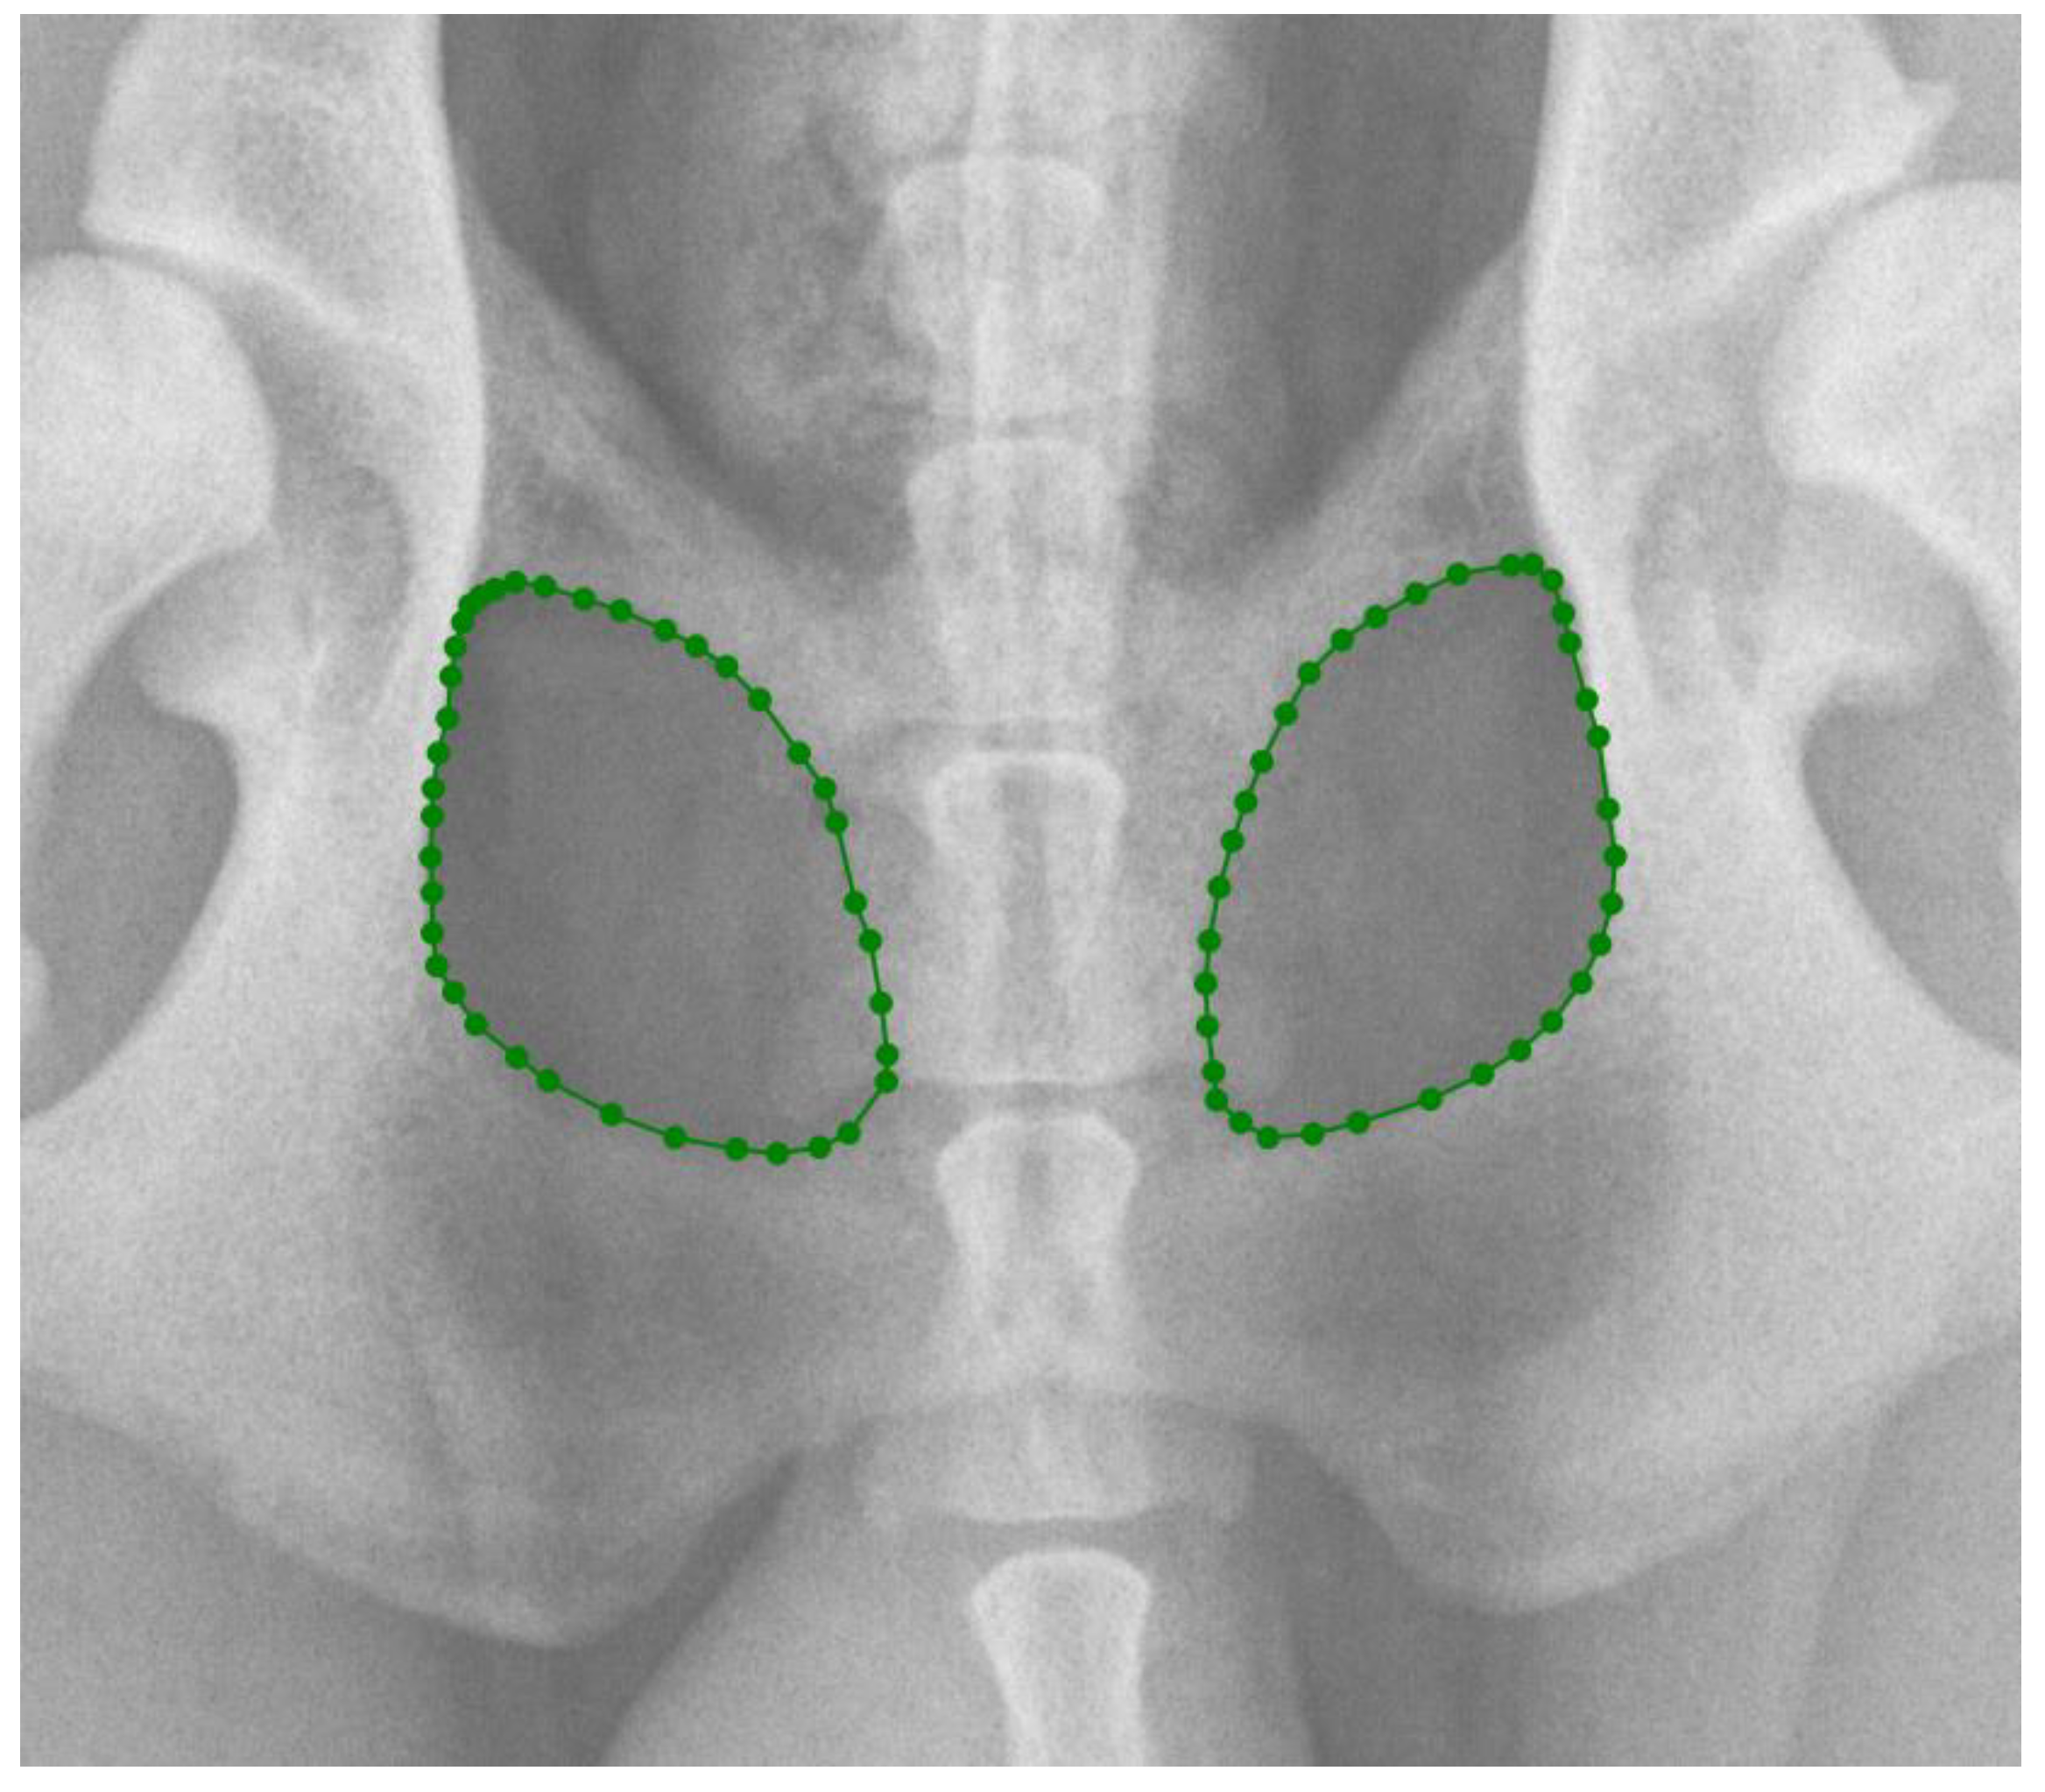

In the first part of the study, 203 radiographs in DICOM format were manually annotated using the polygonal image annotation tool, LabelMe [20], to delineate the right and left obturator foramina. The AIWW was calculated by measuring the widths of the right and left iliac wings in millimeters. A horizontal line was drawn between the dorsal and ventral iliac cortices at the cranial aspect of the sacroiliac joint on both sides (Figure 1). The AIWW was determined by subtracting the width of the right wing from that of the left [10]. The AOFW was calculated by measuring the widths of the right and left obturator foramina in millimeters. A horizontal line was drawn between the medial and lateral aspects of each foramen at its widest points (Figure 1). The AOFW was determined by subtracting the width of the right obturator foramen from that of the left [10]. The AIWW and AOFW, measured in millimeters (x), were used separately to estimate the degrees of pelvic rotation (y) through the following regression equations: y = 0.997x + 0.061 for AIWW and y = 1.644x − 0.912 for AOFW [10]. The AOFA was calculated by measuring the areas of the right and left obturator foramina in square millimeters. For this purpose, the areas were outlined using semantic segmentation, employing pixel-wise labeling to trace the boundaries of both obturator foramina (Figure 2). The AOFA was determined by subtracting the area of the right obturator foramen from that of the left.

Figure 2. Delimitation of the obturator foramina using the LabelMe annotation tool for the calculation of the asymmetry in obturator foramina areas (AOFAs) in ventrodorsal hip extended (VDHE) view. The obturator foramina areas are delimitated by greens points.